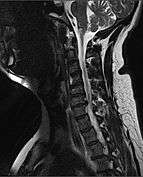

| MRI of fractured and dislocated neck vertebra that is compressing the spinal cord | |